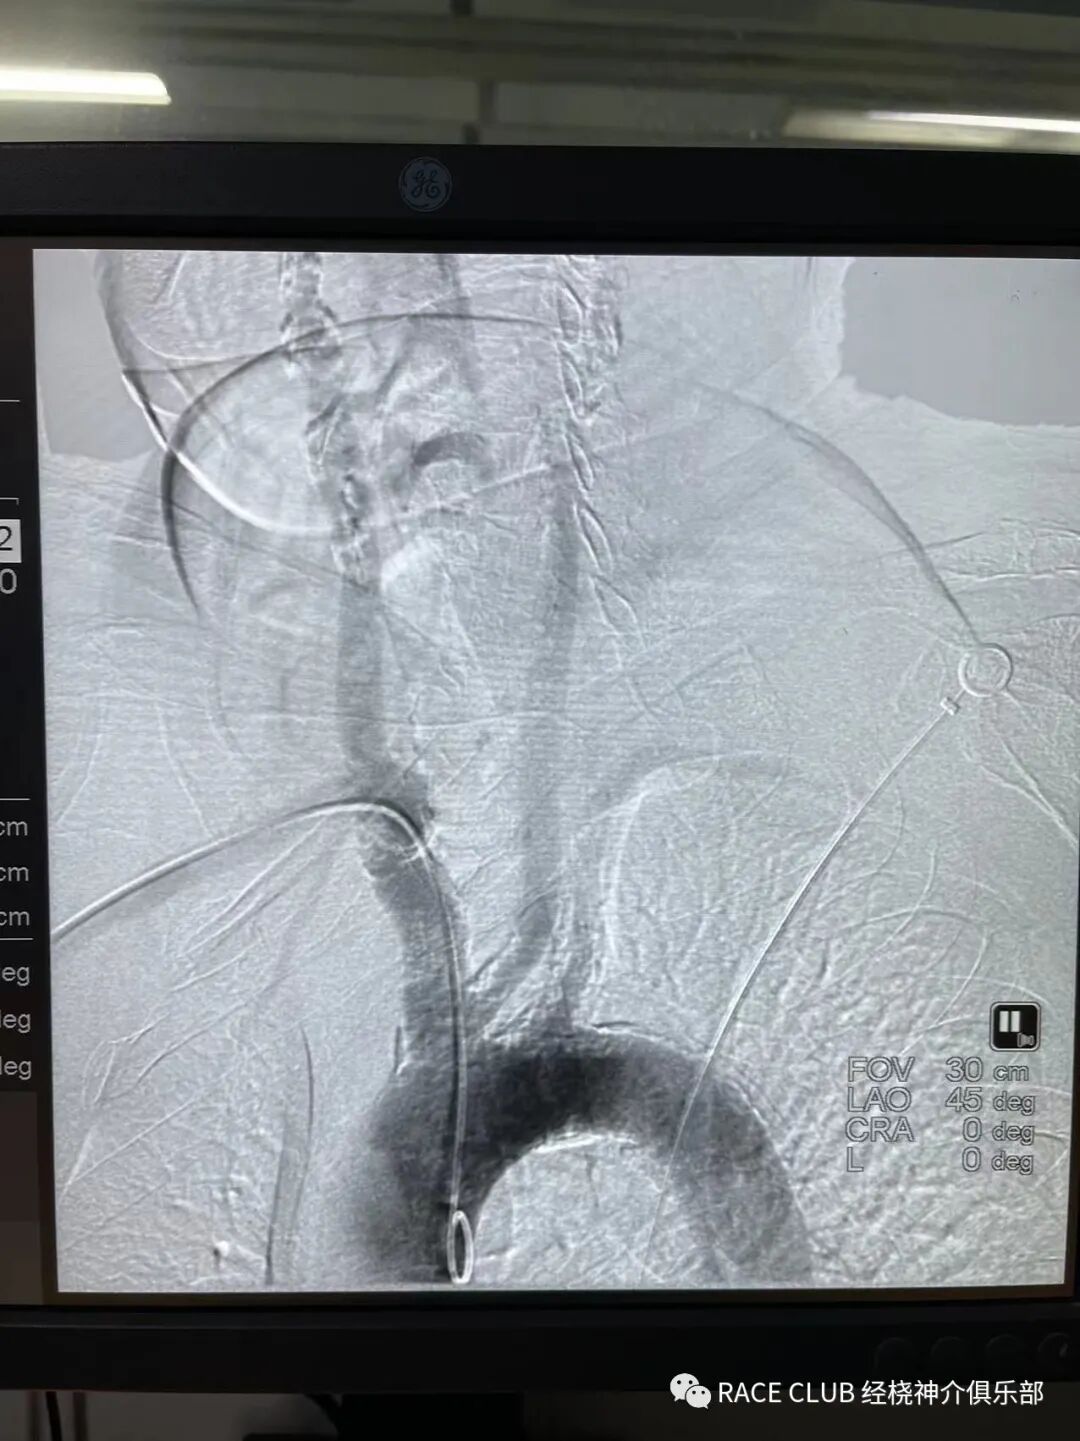

去年九月取栓病人三型弓厉害,桡动脉进的8的股动脉穿刺鞘。

可以的,前两天一个80多老太太取栓经桡也是用的8的鞘。

这个图片是老爷子的。留图片了当时。老太太的没有留图片。

这个股和桡位置都比较高,股这个高度感觉不好压呀,怕覆膜后血肿

股的穿刺点确实高了。怎么上穿刺鞘RACE CLUB 实录6:Q:经桡造影或治疗,穿刺鞘如何选择?_https://www.jmylbn.com_新闻资讯_第46张